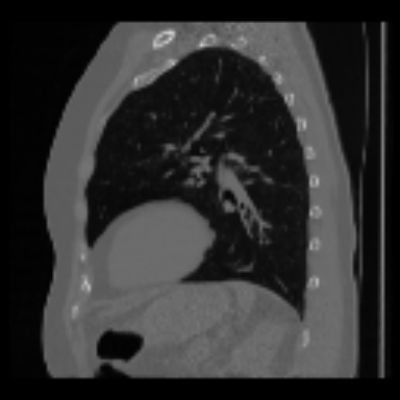

| Real-style X-rays | X2CTGAN | PerX2CT | DX2CT | ||

| PA | ![]() |

Coronal | ![]() |

![]() |

| Lateral | ![]() |

Sagittal | ![]() |

| Axial | ![]() |

The qualitative results in Figure 4 with real-world biplanar X-rays show that the structure of organs in reconstructed CTs by DX2CT better resembles to that of X-rays and DX2CT reconstructs sharper results, compared to the SOTA methods.